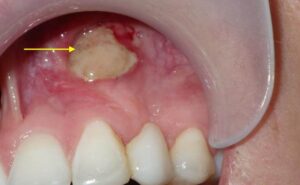

عفونت یا بیماری استخوان (Osteomyelitis or Osteonecrosis)

عفونت استخوان (osteomyelitis) یا مرگ استخوان (osteonecrosis) میتواند باعث بیرون زدگی شود، داروهایی مثل بیسفسفوناتها (برای پوکی استخوان) ریسک را بالا میبرند.

علائم هشدار شامل درد، تورم و بوی بد دهان است، مطالعات نشان میدهد که در بیمارانی که پرتو دریافت کردن، این مشکل شایعتر نیز میباشد.